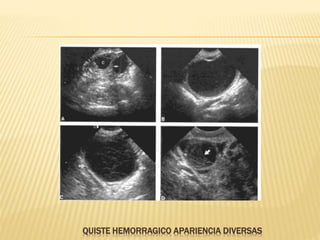

QUISTE HEMORRAGICO APARIENCIA DIVERSAS

QUISTE HEMORRAGICO

 La hemorragia interna puede ocurrir en ambos quistes

funcionales

 Presentan dolor pélvico agudo

 El aspecto ecográfico depende de la cantidad de

hemorragia y del tiempo de la hemorragia en relación al

tiempo de la exploración ecográfica

 Un quiste hemorrágico agudo normalmente es

hiperecogénico y puede simular una masa sólida pero

presenta pared lisa y refuerzo posterior

 En la hemolización del coagulo el patrón interno se torna

complejo, con un patrón reticular que contiene septos y

ecos internos